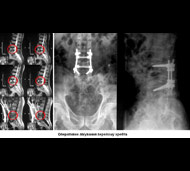

Мета операції - стабілізація хребта металевими конструкціями (імплантантами). Наша клініка була першою в СНД, яка застосувала сучасні конструкції при переломах хребта. Нині ми використовуємо імпортні конструкції типу CD Horison Legacy (США), Atlantis (США), Sextant (США), Socore (Франція). Операції вимагають складної рентгенівської техніки та спеціального інструментарію. При неускладнених переломах хребта хворі можуть ходити після таких операцій уже на другий - третій день. Також в Міжнародному центрі нейрохіургіі вперше в Україні впроваджено метод мініінвазивних операцій при переломах хребта.